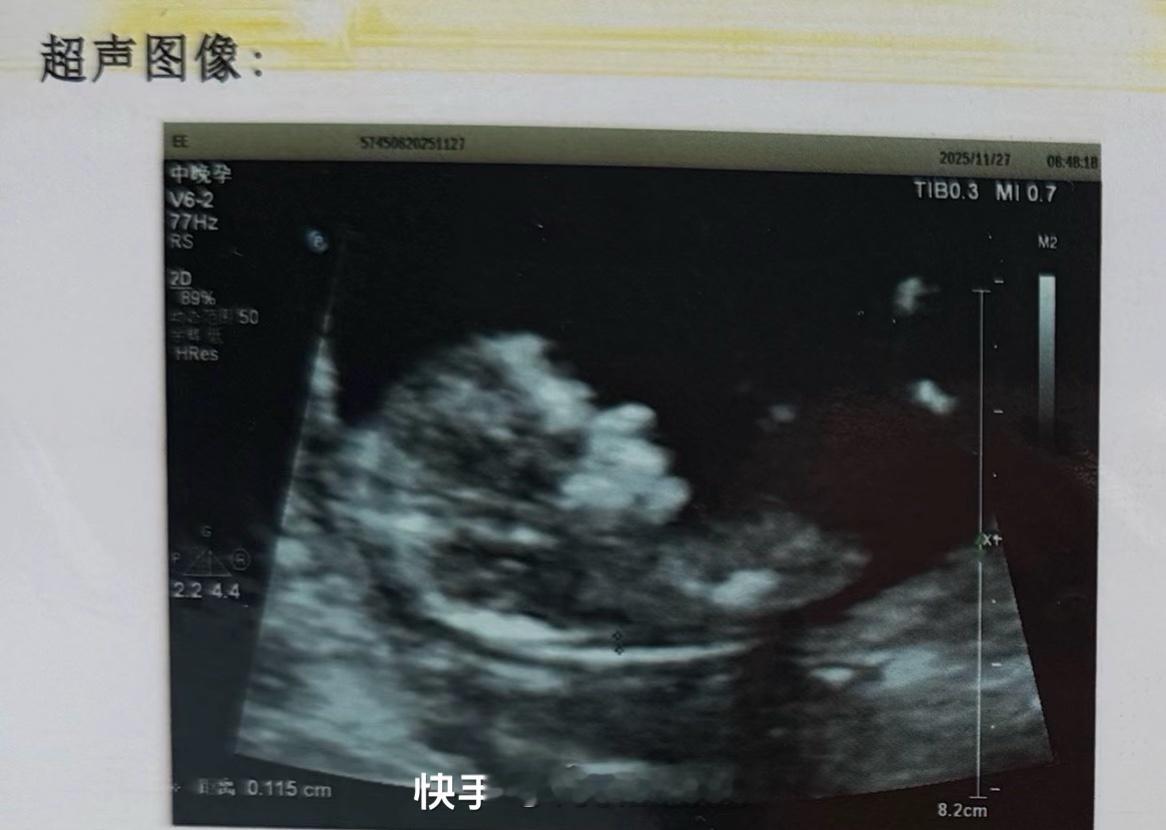

🔴大美闺蜜v5师官宣怀孕!恭喜🎉小孩谢谢你出现在我的生命里,让我多了一个身份,为了你的出现我付出了很多,现在看来都值得,即便身体和心理承受了一些痛苦,但这一刻看到你在我的肚子里舒舒服服的样子,值得了,致敬每一位试管妈妈,虽然辛苦,但也幸福,等待你的到来,为母则刚,你选择了妈妈爸爸,我们会好好的爱你💕